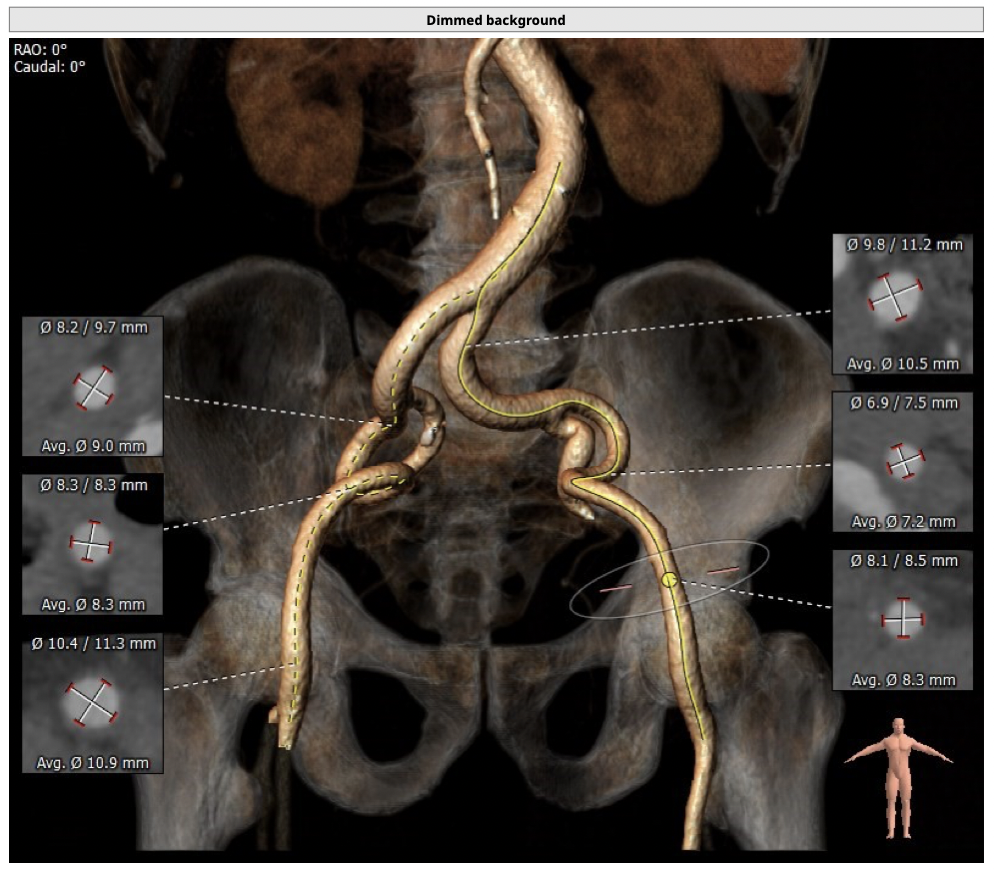

主动脉CT

*髂动脉走形迂曲,升主动脉明显扩张,术中操作需轻柔;

*升主动脉明显扩张,术中操作需轻柔;